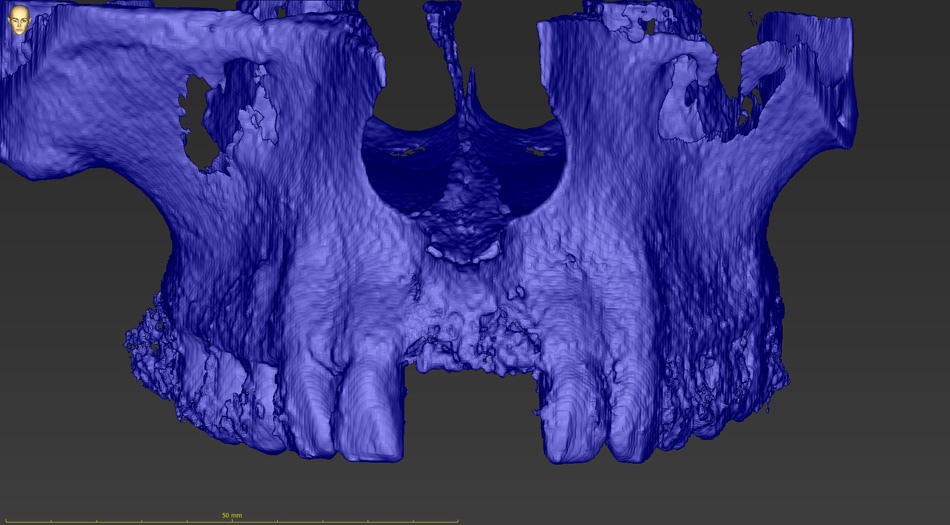

Jedná se o externí plánovací program, spojený se zubní laboratoří a frézovacím centrem, který využívá dat získaných z 3D rentgenu čelisti, otisku zubů a dásně (scanu zubů a dásně) a finálního návrhu protetické náhrady. Tento program umožňuje tříprostorovou počítačovou simulaci při plánování pozic implantátů. Součástí programu je i databáze, ve které mohou být uloženy všechny typy implantátů od všech výrobců, včetně jejich délek, průměrů i tvarů.

Lékař si vytvoří všechny typy zobrazení potřebných pro naplánování – tedy 2D snímky (panoramatický), příčné řezy i 3D model.

Vidí zde i důležité anatomické útvary – čelistní dutinu, průběh nervu atd. Po proměření množství kosti – šířky i výšky vybere z databáze vhodný typ implantátu a umístí ho do požadované lokality. Ihned vidí jeho pozici ve všech 3 rovinách a na všech snímcích i 3D modelu. Může upravovat podle potřeby jeho pozici, sklon atd.

Všechny vybrané a správně umístěné simulované implantáty se ukládají do „počítačové karty“ pacienta s jejich pozicí, délkou, průměrem, typem i sklonem. V programu také lékař navrhuje chirurgické šablony pro řízenou nebo navigovanou implantaci. Lékař i pacient tedy ještě před vlastní operací vidí, jak by mělo ošetření probíhat a vypadat.